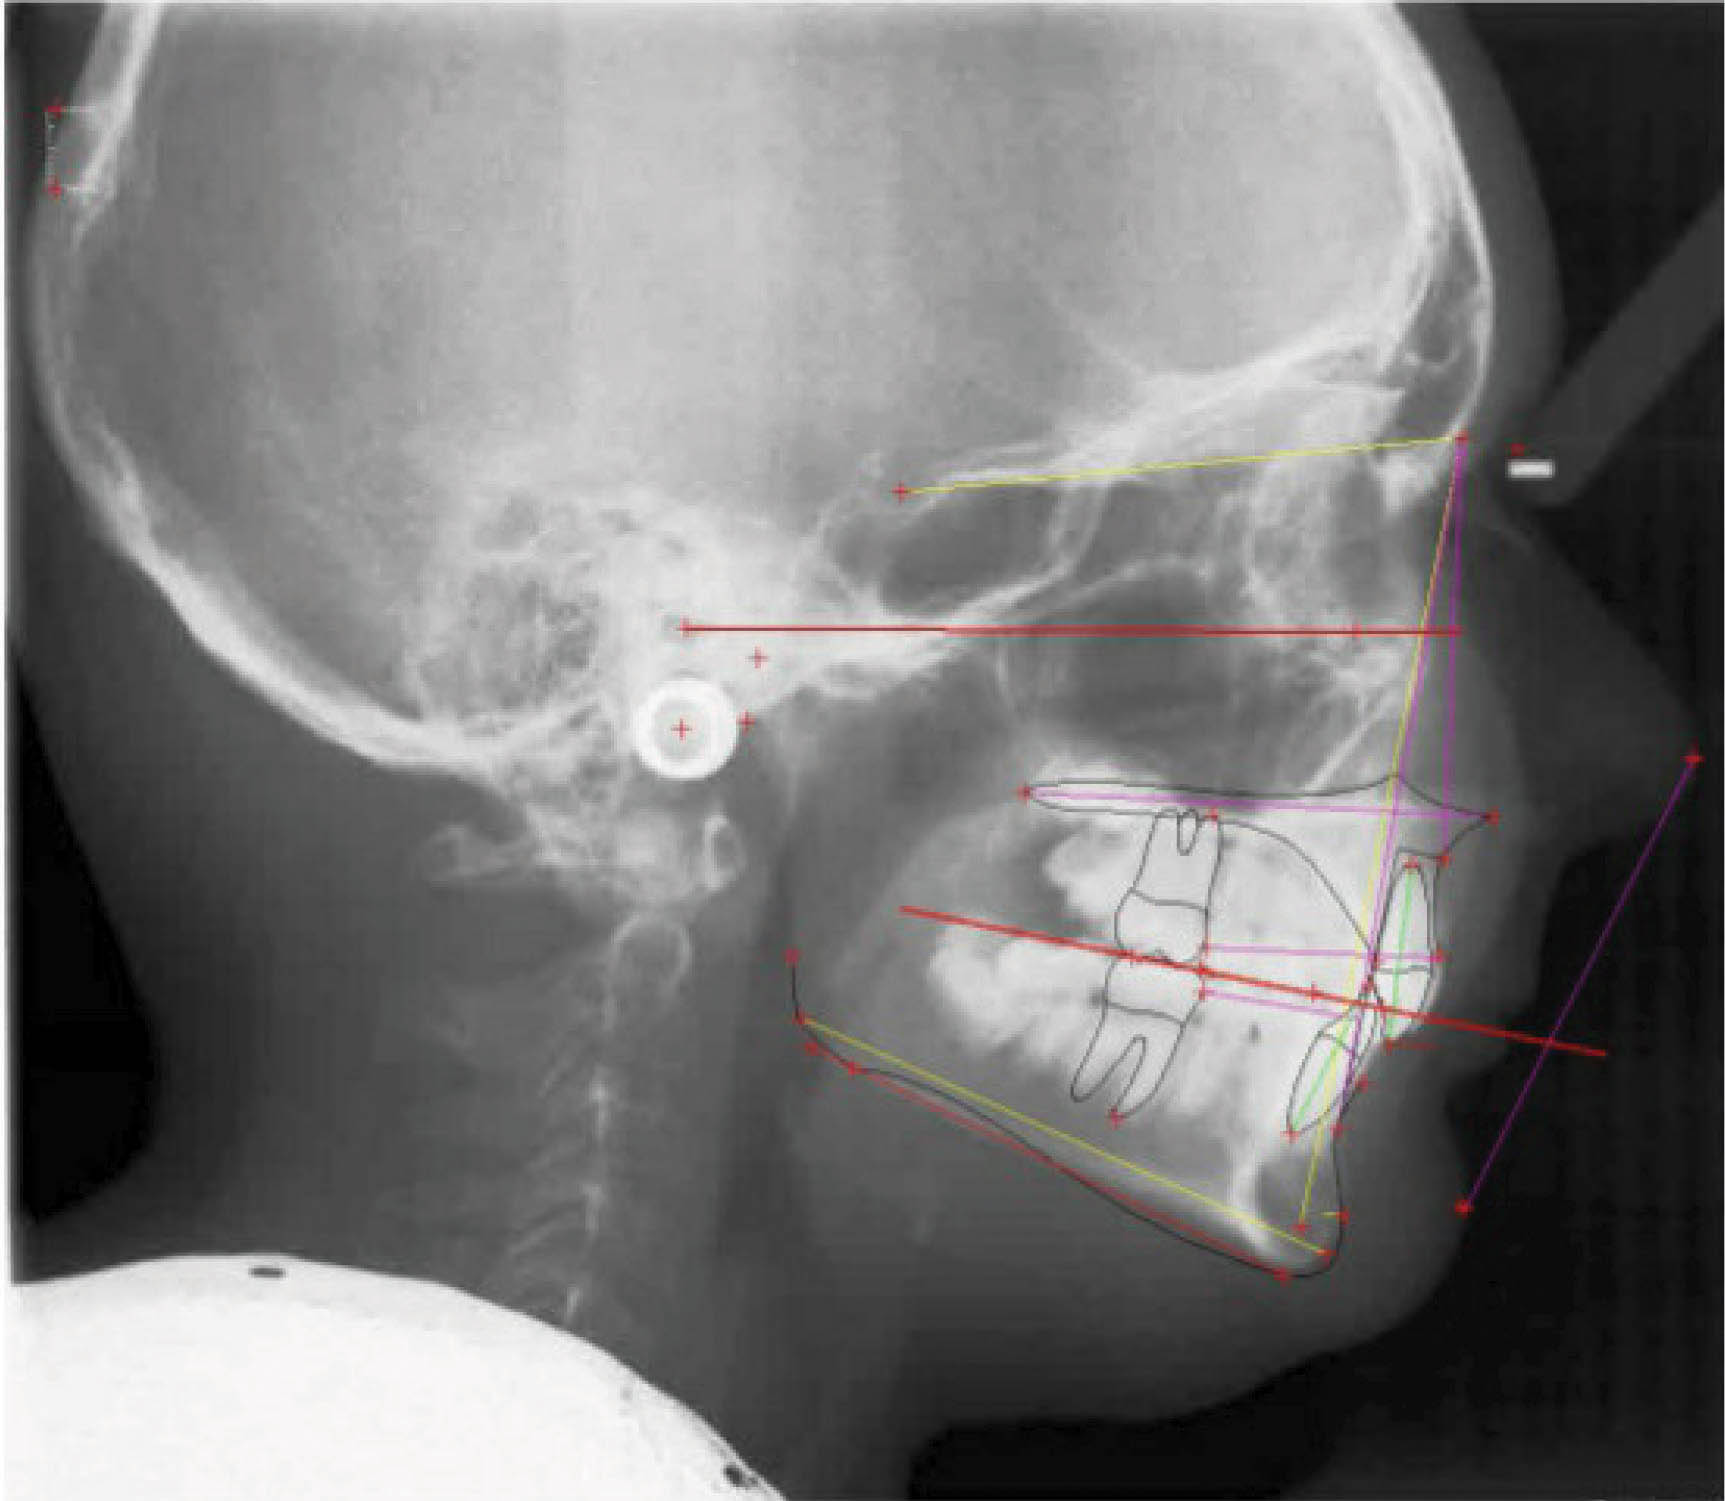

عکس OPG پایان کار (شکل 66-6) طبیعی است. سوپرایمپوز نمودن لترال سفالومتریها (شکل 67-6) پروترود شدن انسیزورهای پایین را نشان میدهد که هم برای رفع کرادینگ و هم برای اینترود نمودن نسبی قدامیها مفید بود.

درمان بیمار ۲۴ ماه به طول انجامید و یک قالب گیری مجدد نیز داش

شکل 67-6